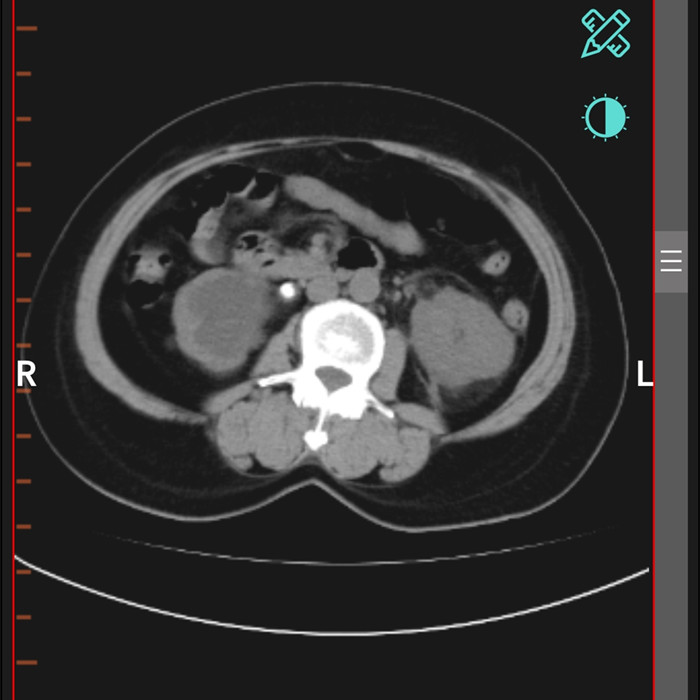

柴女士,62歲,北川縣擂鼓鎮(zhèn)人,因腰右側(cè)疼痛難忍,她來到北川羌族自治縣人民醫(yī)院就診,經(jīng)檢查提示,柴女士右輸尿管上段結(jié)石嵌頓引起重度腎積水。

“要及時解除梗阻,可以行腹腔鏡輸尿管切開取石術(shù)取代開放手術(shù)?!痹谥靹τ碌膸ьI(lǐng)下,這支剛剛成立的“泌尿外科團隊”,僅用了一個半小時就完成了手術(shù)?!案骨荤R輸尿管切開取石術(shù)創(chuàng)傷小,患者腰腹部只有3個戳孔,術(shù)后恢復快?!敝靹τ抡f。